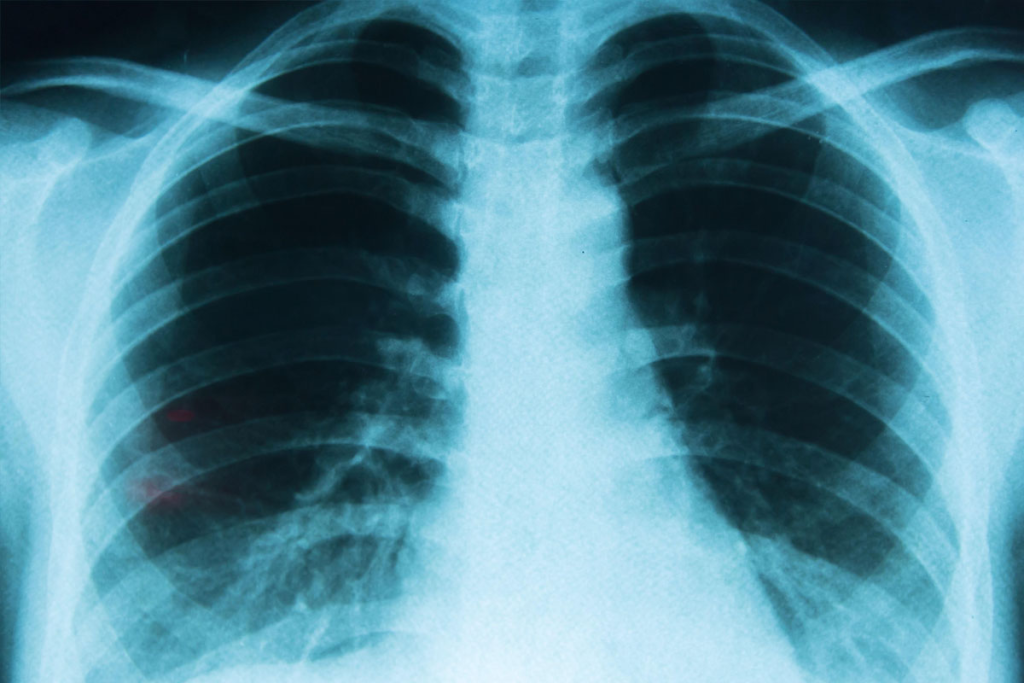

Lung cancer is one of the most common cancers worldwide, and early detection is key for effective treatment. The PET scan has become a popular tool for lung exams because it provides critical insights beyond regular imaging. A lung PET scan is an advanced test that uses a small amount of radioactive substance to detect disease activity in the lungs. Unlike MRI and CT scans, it shows how lung cells are functioning, not just their structure. This helps doctors diagnose lung cancer, track its progression, and plan targeted treatment options. Why doctor recommend PET scan is clear: it delivers precise information that guides better treatment decisions, making it a vital tool in the fight against lung cancer.

PET scans are different from CT or MRI scans. While CT and MRI show what organs look like, PET scans show how they function. This is important because PET scans can spot changes at the cellular level before other scans can.

PET scans are key in finding and managing lung cancer. They show how active lung tissues are, helping to tell if something is cancerous. Early detection and accurate diagnosis are critical in improving patient outcomes, and PET scans play a vital role in this process.

PET scans are more accurate than other imaging methods. They give detailed info on tissue activity, not always seen in CT or MRI scans. The ability to assess metabolic activity makes PET scans useful in staging cancer and evaluating treatment response.